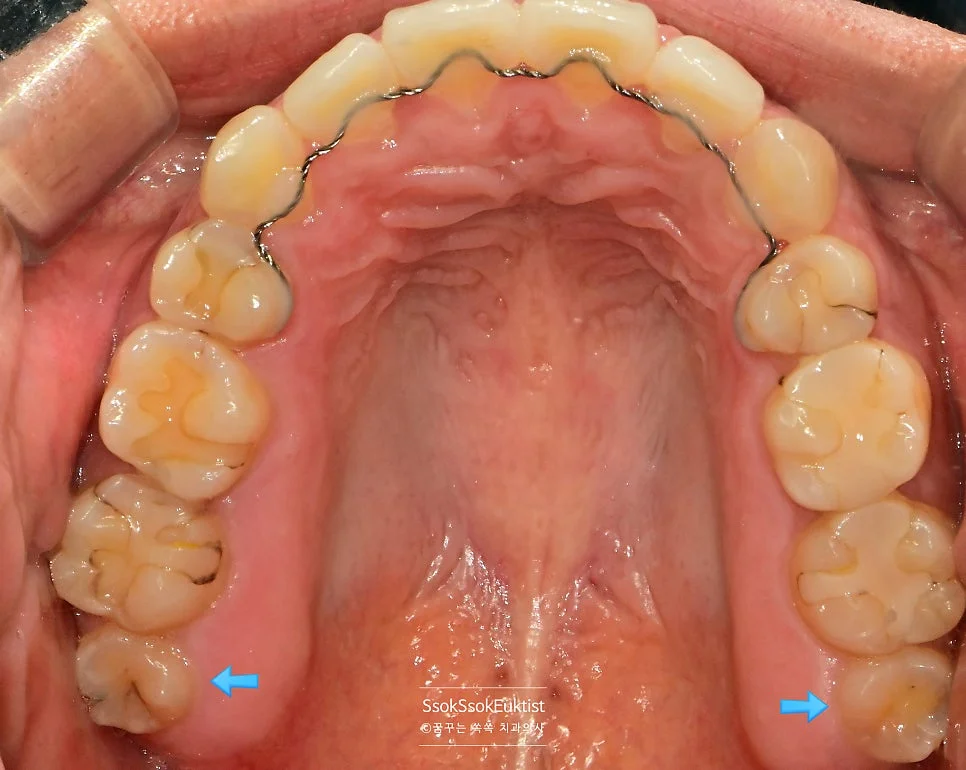

구강 전체 사랑니 4개 진단 사진

구강 정면 사진 — 사랑니 4개가 모두 존재하는 상태

사랑니는 4개가 다 있고, 다 발치해야 하는 상황이네요^^

파란 화살표로 표시되어 있는 치아가 사랑니입니다! 위 사랑니는 크기가 좀 작지만 비교적 얌전히 나있는데요!

아래 두 개의 사랑니를 보면 머리부터 충치가 상당히 진행되어 있는 것을 볼 수 있습니다. 아래 사랑니는 매복 사랑니이기 때문에 발치를 해야 하고, 위 사랑니는 아래 사랑니를 제거하면 닿는 치아가 없어 필요 없고 관리만 안 되는 사랑니이기에 발치를 하는 것을 추천합니다!^^